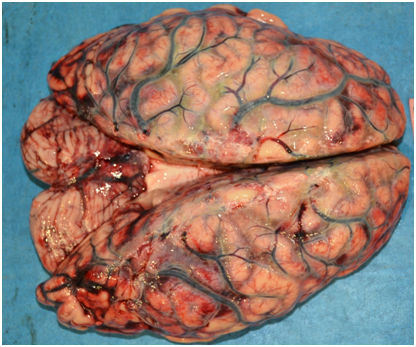

A retired male school teacher of 69years of age had been apparently healthy until he developed severe abdominal pain as the first symptom. He sought treatment from a consultant physician. In the second visit a CT scan of the abdomen was done revealing a distal cholangiocarcinoma. For patients with the above condition, had the diagnosis been made early enough, pancreaticoduodenectomy (also called Whipple procedure) remains the best surgical option. Within a period of around three months of the diagnosis, Whipple surgery was performed on the patient in a specialized surgical unit in a tertiary care hospital in government sector. The operation was uneventful and he was discharged on the eighth day post-op. All necessary advice regarding postoperative care was given and he was referred to the surgical clinic to be seen at once-a-week intervals initially. He was well until two weeks after the surgery. Wound toileting was done every other day. At the end of the second week his wound on the surgical site appeared to be infected. He was admitted to the same surgical unit where debridement of the skin wound alone had been performed by a junior doctor. No ultrasound or any other form of imaging of the abdomen was performed. His abdomen was not examined by a consultant surgeon with a view of excluding any possibility of internal communication of the apparent cutaneous wound. He was discharged the same day. At home his general condition started to deteriorate further. The cutaneous surgical wound gradually got worsened despite strict adherence to instructions given by the ward upon discharge following wound debridement. More and more fowl-smelling purulent discharge was oozing from the wound. He developed high spiky fever with chills and rigors. His urine output was reduced and consciousness was frequently clouded. This deterioration took place rapidly within three days where he was re-admitted to the same unit on the eighteenth day post-op in a state of unconsciousness. The GCS was 3/15 and the blood pressure was unrecordable. The non-contrast CT brain was unremarkable. Haematological and biochemical investigations were in favour of sepsis with metabolic acidosis. The next day (day 20 post-op) he was pronounced dead. As the senior next of kin of the deceased had raised several medico-legal issues including the source of sepsis and its contribution to surgical procedure and the death being one with a potential for subsequent allegation of medical malpractice, an inquest into the death was requested to be followed by a judicial autopsy. At autopsy, the body was that of a thin built male with no external features of dehydration or emaciation. Mild icterus was noted. The sub-costal Kocher incision measured 28cmX2cm with necrotizing margins with visible underlying muscle. With the involvement of the distant organs in the form of peritonitis and meningitis etc. (discussed later), the surgical site infection could easily and safely be classified as “organ or space Surgical Site Infection (SSI)” (Figure 1).5

Routine dissection of all organs was done during internal examination. The brain weighed 1400g. It was dusky red in colour with marked congestion and features of meningitis. Cut sections revealed areas of necrosis with clear demarcation of grey and white matter (Figure 2). His neck structures were unremarkable. The lungs were congested and beefy red in colour, the right lung weighing 360g and the left lung 350g. No features of pulmonary embolism were evident to the naked eye. The pleural cavities contained blood-stained serous fluid, 160 ml and 200ml respectively on the left and the right sides. The pericardium contained 75ml of purulent fluid with dense adhesions to the outer surface of the heart (Figure 3). The heart weighed 360g. Major coronary arteries and their principal branches were not calcified and the maximum atherosclerotic narrowing was 30%. The heart valves appeared unremarkable.